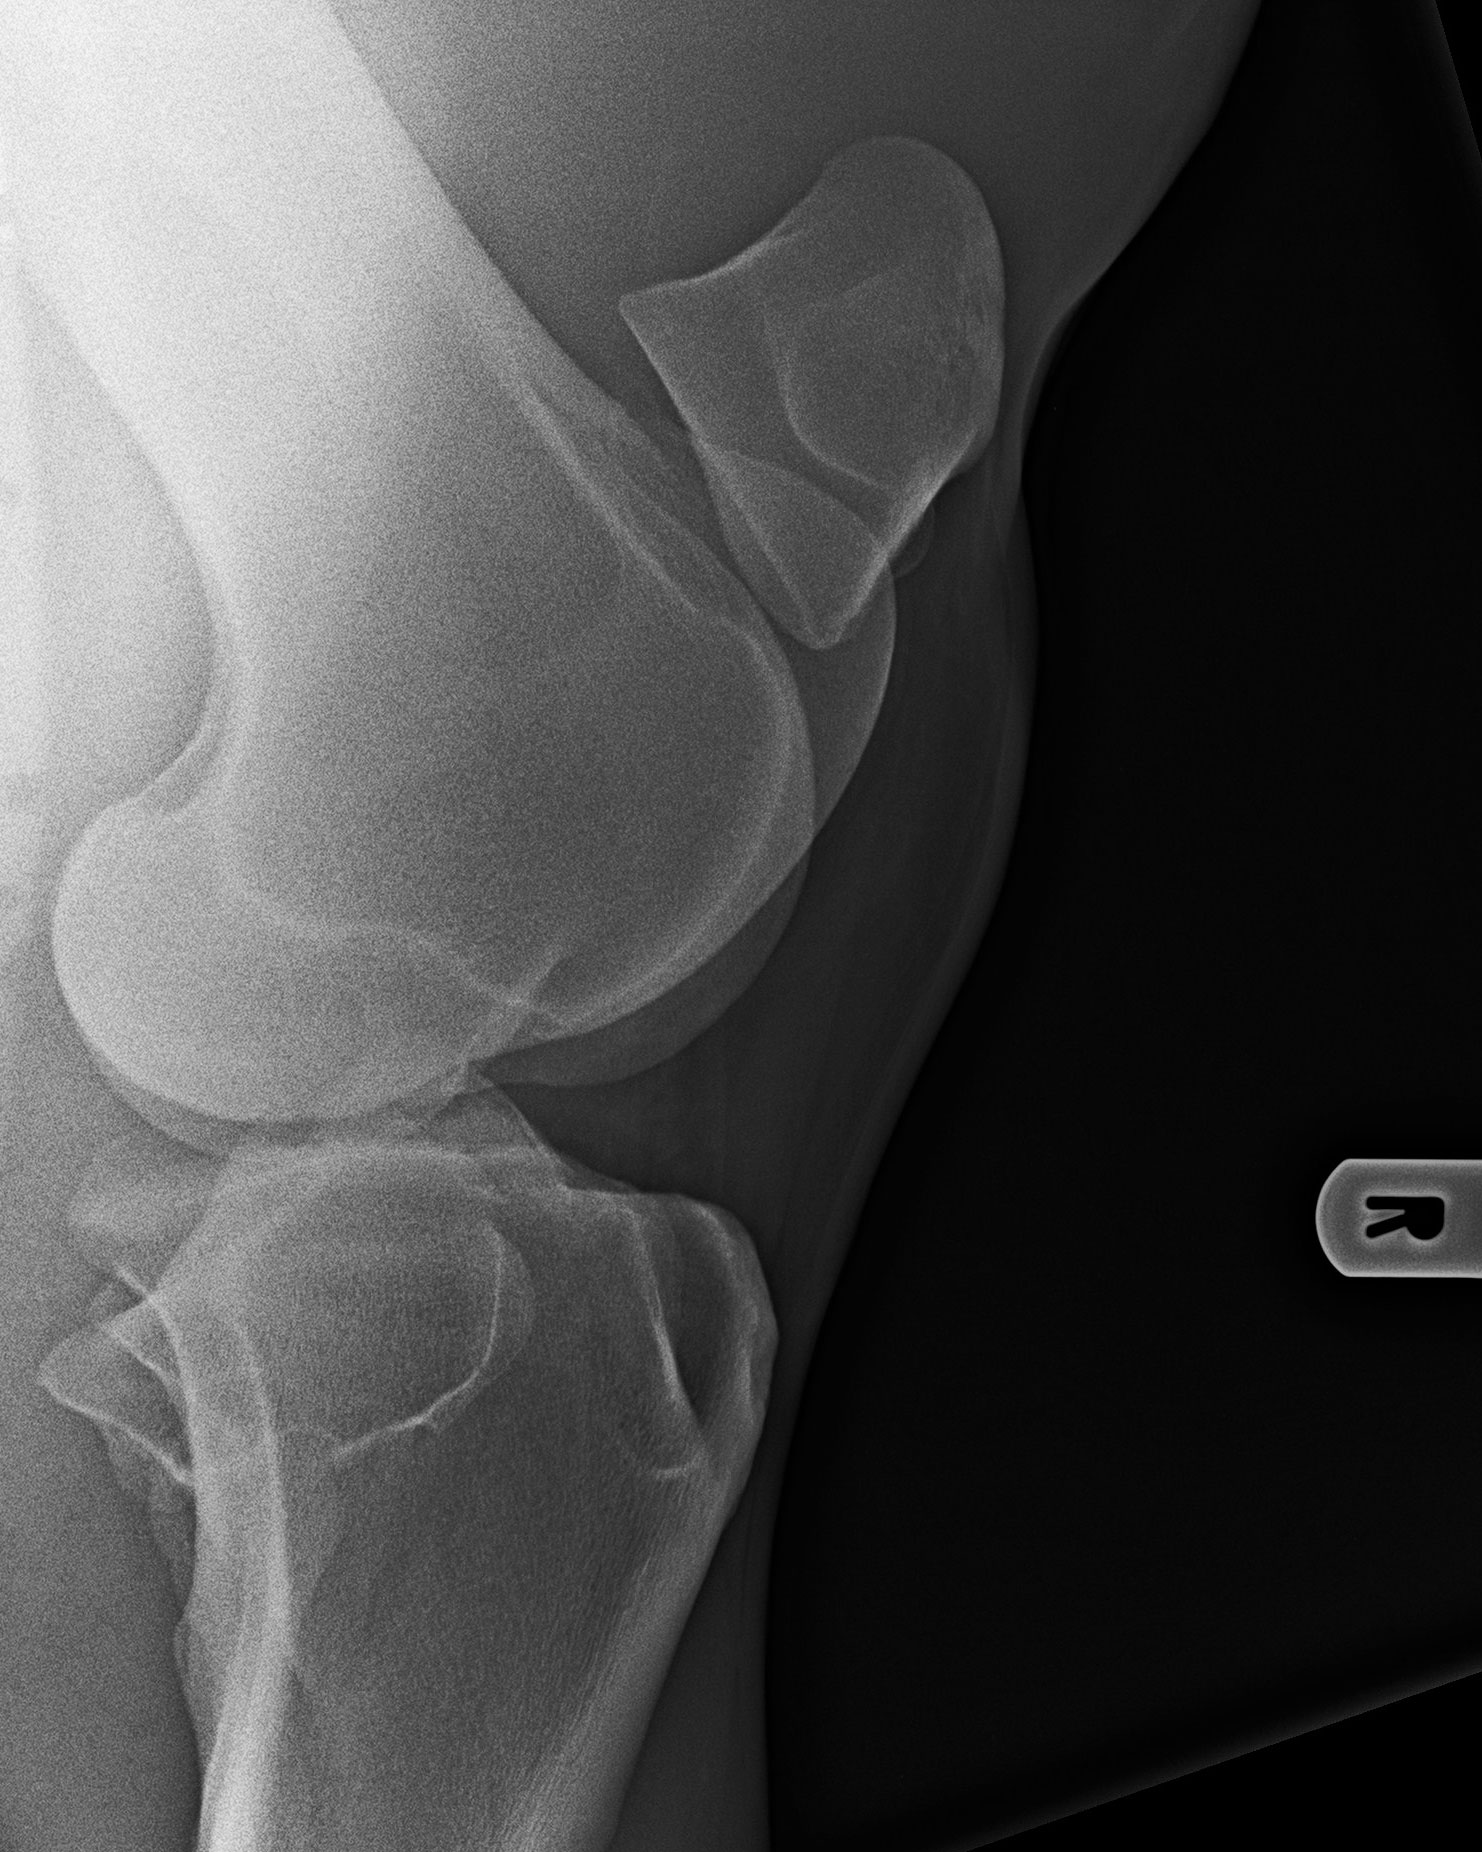

Kniegelenk - 90°-Aufnahme